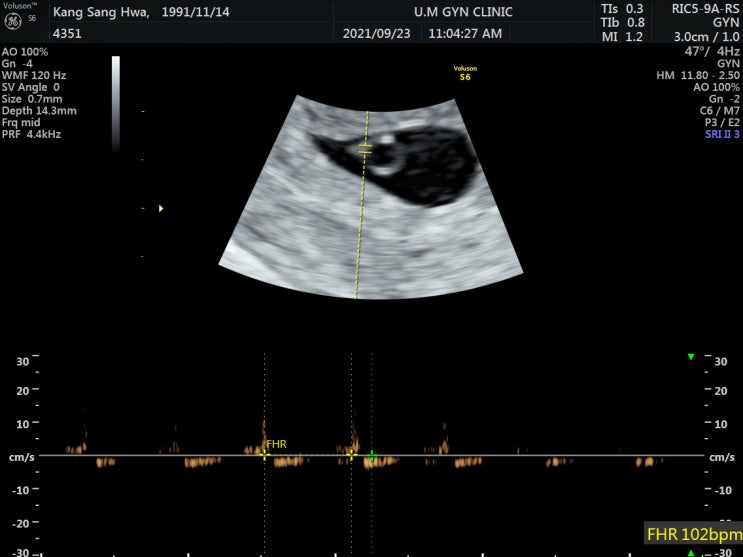

[찰떡일기??] 임신5-7주(임신초기): 임신초기증상/입덧/주수별심장박동수